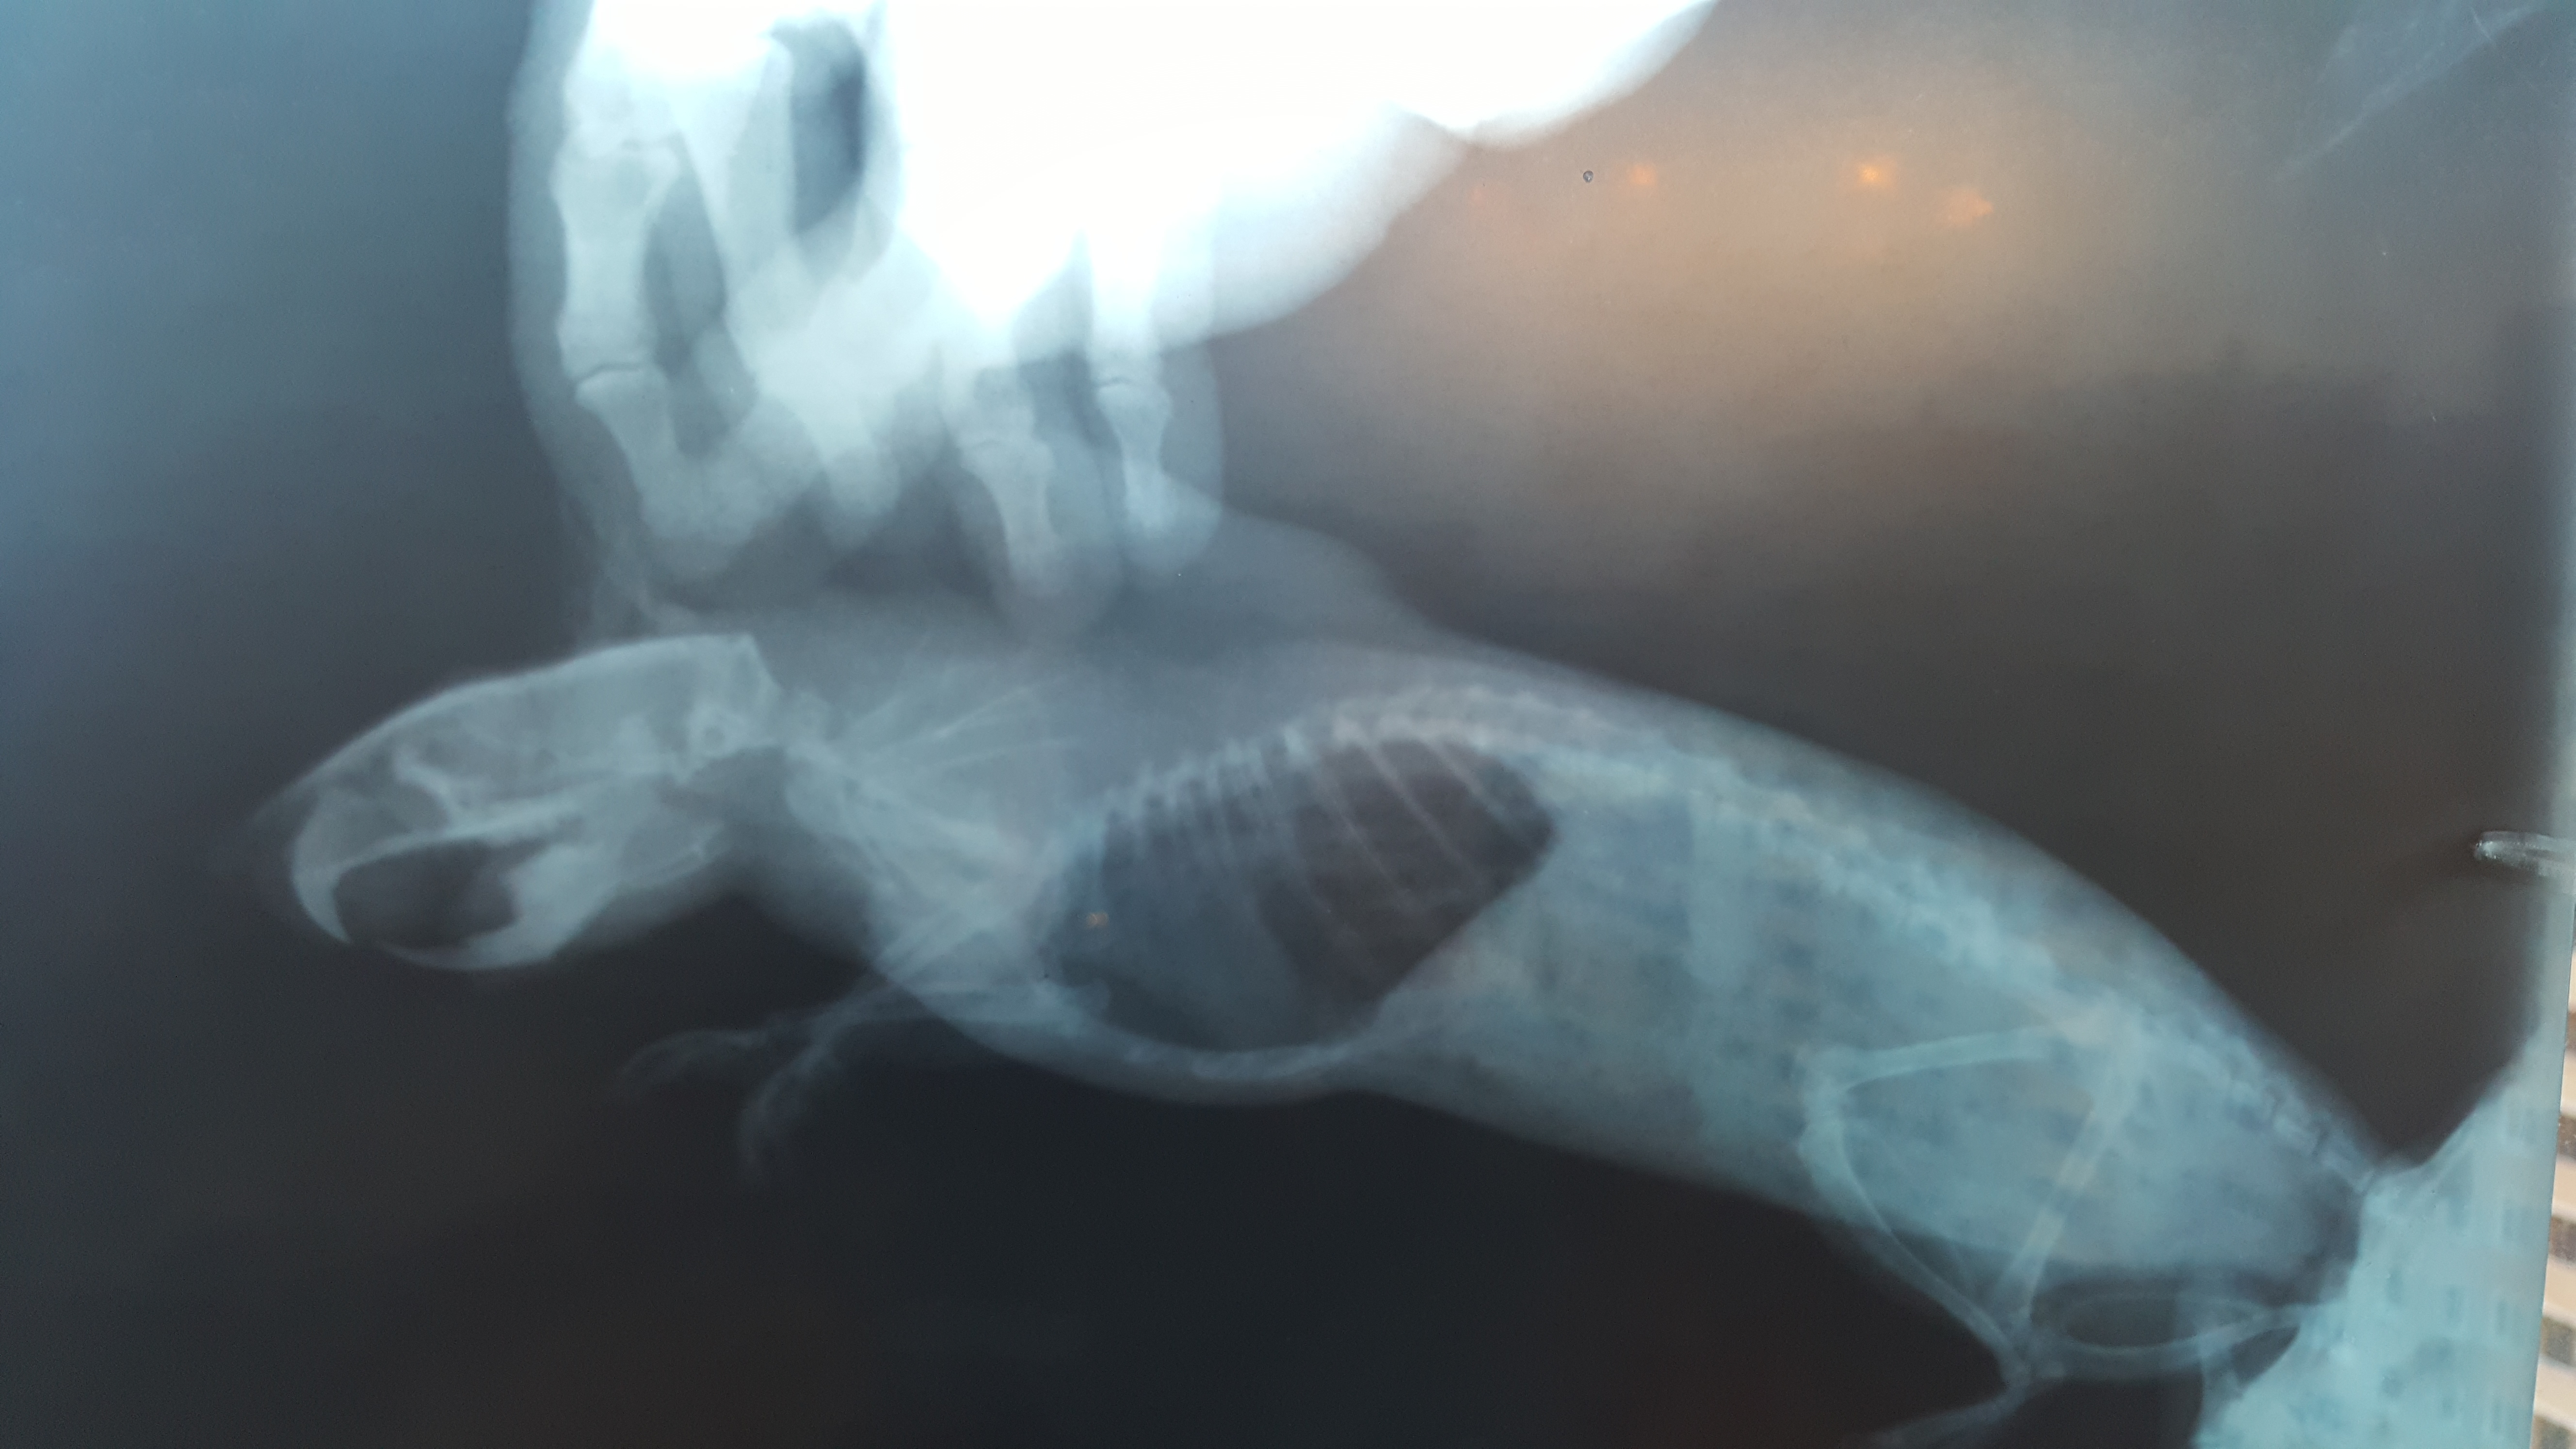

13 дней назад (11.04.18) вернулись из отпуска (оставляли крысика бабушке) и застали такую картину. Тяжелое дыхание грудной клеткой, кашляет порфирином из рта, вялость, ухудшение аппетита, активность 30%. Поехали к ветеринару, диагноз - отек легких (застойная пневмония), подозрение на перикардит и онкопроцесс.